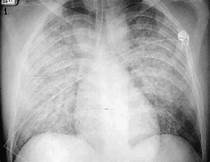

Sindrome cardiopulmonar por hantavirus (SCPH): infiltrado pulmonar com depressão miocardica